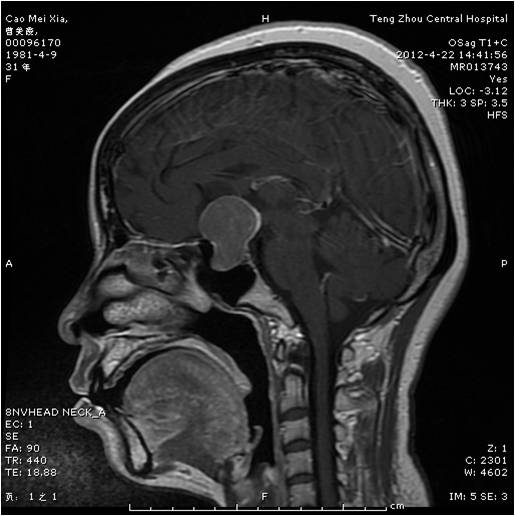

垂體瘤術前 垂體瘤術后